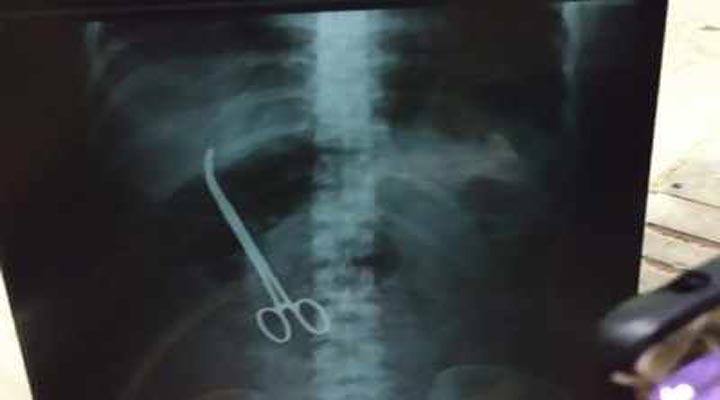

నిమ్స్ ఆసుపత్రిలో దారుణం చోటుచేసుకుంది. వైద్యుల నిర్లక్ష్యం రోగి ప్రాణాల మీదకు తెచ్చింది. శస్త్రచికిత్స సమయంలో ఆపరేషన్కు ఉపయోగించిన కత్తెరను వైద్యులు కడుపులోనే మరిచిపోయారు. దీంతో రోగి బంధువులు ఆందోళనకు దిగారు. మహేశ్వరి (33)అనే మహిళకు మూడు నెలల క్రితం హెర్నియా శస్త్రచికిత్స జరిగింది. అనంతరం ఆస్పత్రి నుంచి డిశ్చార్జి అయ్యింది. అయితే, గత 15 రోజులుగా తరచూ కడుపునొప్పి రావడంతో రోగి మరోసారి ఆస్పత్రికి రావడంతో విషయం వెలుగు చూసింది. వివిధ పరీక్షలు నిర్వహించిన వైద్యులు కడుపులో కత్తెర ఉన్న విషయాన్ని గుర్తించారు. వైద్యుల నిర్లక్ష్యాన్ని నిరసిస్తూ ఆస్పత్రి ఎదుట రోగి బంధువులు ఆందోళనకు దిగారు. పంజాగుట్ట పోలీస్స్టేషన్లో ఫిర్యాదు చేశారు. కత్తెరను తొలగించేందుకు మహిళకు వైద్యులు శస్త్ర చికిత్స చేపట్టారు.

మహిళ కడుపులో కత్తెర మరిచిపోయిన ఘటన దురదృష్టకరమని నిమ్స్ డైరెక్టర్ మనోహర్ పేర్కొన్నారు. మహిళకు శస్త్ర చికిత్స చేసి కత్తెరను తొలగించామన్నారు. ఈ ఘటనపై ముగ్గురు సభ్యులతో కూడిన కమిటీని నియమించామని తెలిపారు. ఇటువంటి సంఘటన గత 30 ఏళ్లలో ఎప్పుడూ జరగలేదన్నారు.